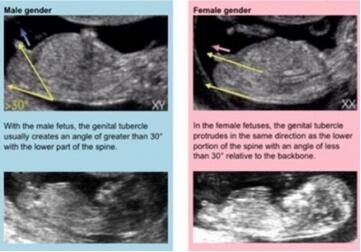

具体方法:主要看超声检查报告上的胎儿的尾椎骨末端和小腹之间的突出点,即生殖器位置。

判断依据:NT检查时男孩和女孩的生殖器形状是一样的,但毕竟男女有别,还是有区别的。如果是女孩,生殖器是直接向外突出,没有向上的角度,看上去比较平,与躯体的角度一般不会超过30度。如果生殖器是向上挑则是男孩。